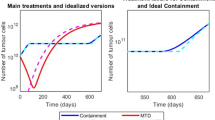

4.3 Evaluation of Treatment Strategies

Using the Moran model with three cell types (healthy \(h,\) cancerous \(c\), and mutant \(m\)), different treatment strategies were tested and compared (Fig. 5A): applying the maximum tolerated dose (MTD) after mutant growths arise, earlier dosing, dual dosing, sustained dosing, and waning treatment. Here, the MTD is assumed for all simulations except the sustained dosage and waning treatment. The sustained dosage is a reduced dosage (lower treatment efficacy) that is applied for a longer period, and the waning treatment is an exponential decrease of the effect of treatment to capture pharmacokinetic drug dynamics. The dual dosing treatment considered that the mutant cancer was targeted in the first dose and that the second dose targeted the original cancer. See Fig. 5B–F for the mean and standard deviation of 1000 model simulations.

Comparisons between different treatment methods and models. A Descriptions of the five treatment methods considered in (B–F): a MTD, an early MTD, a dual dosage (one targeting the mutant followed by one targeting the cancer), a sustained low dose and a waning treatment. B–F Simulations of cancer growth under varying treatment strategies, average and standard deviation of \({n}_{total}=1000\). B, C Single high dosages applied for \({t}_{length}=5000\) cell divisions between the vertical dashed lines B after the mutant clone is expected to arise and C before the mutant clone is expected to arise, i.e. early treatment. D Dual dosing with the first targeting the mutant cancer clone and the second targeting the original cancer clone. E Sustained dosing with an efficacy one fifth of that in other tests. F High dosage with a waning drug concentration modelled by the blue dashed line. G, H Proportion of simulations (here \({f}_{m}=1.6\) and \(M=\mathrm{20,000}\)) with varying \({r}_{m}\) and \({\text{eff}}_{m}\) where mutant cells reach a population of \(0.5N\) under G single high dosage treatment, and H sustained treatment with efficacy scaled by 1/3 and length scaled by 5. Corresponding two parameter plots for the original cancer are given in Figure S3D (Color figure online)

In general, the presence of a mutated cancer clone provides the cancer growth with an inherent treatment resistance which makes treatment difficult. In certain cases, particularly the MTD, sustained treatment and waning treatment, the presence of the drug only aided the growth of the mutated clone by reducing the original cancer clone. As such, applying the MTD can be effective assuming that the treatment is effective towards the mutated clone or if the treatment dose is high enough, but can fail to eliminate the mutated cancer otherwise (see Fig. 5B). Sustained treatment often fails similarly since the reduced dosage is not strong enough to eliminate the mutated cancer (see Fig. 5E).

This motivates the use of early dosing which tends to eliminate the cancer before any mutation arises and does not require a large dosage if targeted towards the original cancer, as seen in Fig. 5C. Finally, dual dosing was considered to target the mutated cancer in a first dosage to reduce or eliminate it, and then apply a second dose targeted towards the original clone. This provided varying results depending on mutation (see Fig. 5D), but it is again determined that intra-clonal heterogeneity presents challenging resistances to treatment.

An alternative treatment model considering a waning effect on the drug’s concentration is considered in Fig. 5F, where the concentration is modelled by a decaying exponential based on the drug’s half-life. In this case, the half-life is arbitrarily selected to be 5000 cell divisions, though this may be more appropriately selected for specific cases. Here, the waning treatment model represents a more natural transition between active and ineffective treatment, in this case showing results less promising than consistently administering the MTD, and more promising than administering a consistent sustained dose. Individual model trajectories for the five treatment scenarios are plotted in Figure S4 and corresponding violin and scatter plots for the final proportion of healthy, cancer and mutant cells is given in Figure S5–S6. Figure 5G, H compare the mutant cancer (type \(m\)) responses to treatment with the MTD and sustained treatment respectively, where the mutation rate and efficacy against mutant cells vary. These plots consider the proportion of simulations where mutant cells grow to at least \(50\%\) of the total cell population \(N\) within \(M=\mathrm{20,000}\) cell divisions. Additionally in Figures S3D, a similar comparison is made for the original cancer cell type (type \(c\)). For the selected parameters, the original cancer (cell type \(c\)) will almost never reach \(50\%\) of \(N\), which is likely due to tunneling rather than treatment, as the mutated cancer is expected to take over quickly. Figure 5G, H show that the mutated cancer cell clone (type \(m\)) is more likely to grow to a substantial size in the sustained treatment scenario if the mutation rate is high and treatment is not as effective against that cell type, as expected. Specifically using the MTD in this case, low efficacy is required for the mutated cancer to have a non-zero chance of reaching \(50\%\) of \(N\). It is evident that treatment with the MTD is overall more effective than sustained treatment when changes in efficacy and mutation rate are considered. Some selections of these parameters can facilitate effective sustained treatment such as zero mutation rate or a treatment efficacy of \(100\%\), however these selections are not practical.

We then considered these parameters in our previous treatment scenarios from Fig. 5A, however, particularly focussing on MTD. Results shown in Fig. 6C compare a single high-dose injection (MTD) to a sustained low-dose injection, both with waning drug concentration after treatment concludes. It is seen from the typical simulations that this sustained treatment with Herceptin does not have a strong impact on the cancer’s growth, though the single high-dose treatment is able to almost eradicate the cancer entirely, however, regrowth eventually occurs.